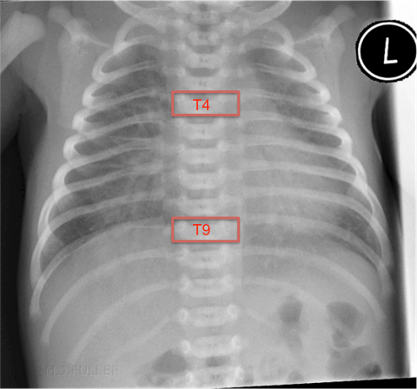

The optimal position for the distal tip of a PICC line is in the SVC or IVC but clearly outside the cardiac silhouette.

- For a PICC line inserted in an upper limb or scalp vein the tip should be within the SVC but above T4

- For a PICC line inserted in a lower limb the tip should be within the IVC but below T9 and lie to the right side of the spinal column. (this will require care to ensure the baby is not rotated at the time the X-ray is taken)

Fig.2 Neonatal CXR with maximal insertion landmarks